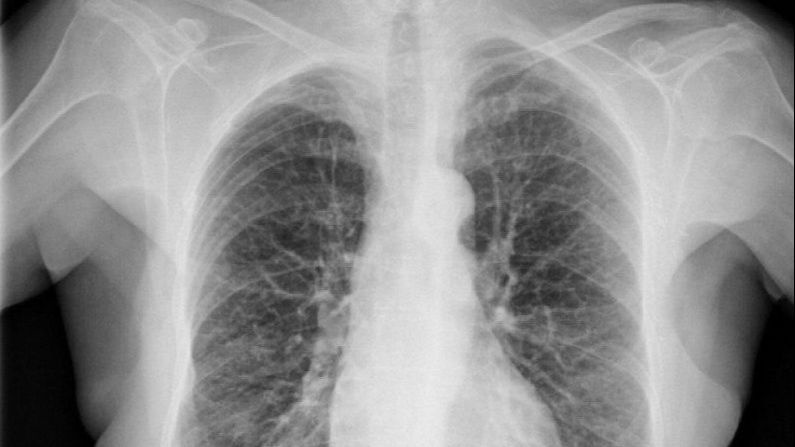

Sevilla/Investigadores andaluces han desarrollado un modelo inteligente que facilita el diagnóstico temprano de enfermedades pulmonares, un proyecto basado en IA que detecta de manera automática posibles alteraciones en radiografías de tórax.

Investigadores de los dos centros han desarrollado un modelo basado en IA que mejora la detección automática de posibles alteraciones en radiografías de tórax, una herramienta que se presenta como un aliado rápido y preciso para neumólogos y radiólogos en el diagnóstico de enfermedades pulmonares.

Algunas anomalías que se producen en el pulmón con patologías como la silicosis se presentan de forma sutil en sus fases iniciales, lo que puede dar lugar a interpretaciones clínicas diferentes.

El estudio, que publica la revista Expert Systems with Applications, explica cómo expertos en neumología e inteligencia artificial han evaluado un nuevo modelo, denominado Mamba-YOLOvX, que permite localizar lesiones de diversos tamaños de forma rápida y efectiva gracias a algoritmos de aprendizaje automático que utilizan una arquitectura conocida como redes neuronales convolucionales.

Así, el sistema aprende a reconocer y diferenciar objetos analizando miles de imágenes para entrenar a la IA con miles de radiografías diferentes.

“En muchas ocasiones, algunas lesiones pulmonares pueden pasar desapercibidas en los exámenes radiológicos, dada la gran dificultad en la interpretación de esta modalidad de imagen médica”, ha explicado el investigador de la Universidad de Cádiz Daniel Sánchez Morillo, coautor del artículo.

Ha añadido que los resultados obtenidos con el modelo han supuesto una mejora en la precisión de diagnóstico con respecto a otros métodos desarrollados recientemente, especialmente cuando se trata de lesiones pequeñas.

El sistema incorpora mecanismos de atención espacial y de canal, que funcionan como filtros inteligentes capaces de concentrarse sólo en las zonas relevantes de la radiografía y en las características más útiles, ignorando lo que no aporta información.

También incluye bloques de escaneo selectivo, que analizan la imagen en distintas resoluciones y permiten identificar lesiones muy pequeñas, que suelen pasar desapercibidas.

Para una mejora en el entrenamiento del modelo, se han empleado datos de distintos centros hospitalarios y una estrategia conocida como aumento de datos, en las que se segmentan las costillas y se alinean puntos clave del tórax para generar nuevas imágenes homogéneas desde una perspectiva anatómica.